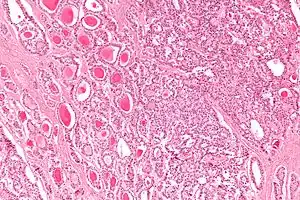

| Micrograph of a strumal carcinoid. H&E stain. | |

The strumal carcinoid is a type of monodermal teratoma with histomorphologic features of (1) the thyroid gland and (2) a neuroendocrine tumour (carcinoid).[1][2]